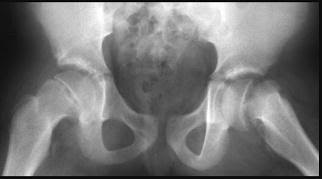

Be vigilant for childhood conditions such as Perthes diseases in 5-10 year olds (see figure 14 [3]) and Slipped Upper Femoral Epiphyses in 10-15 year olds (see figure 15).

Figure 14

Figure 15

Missing these can condemn the child to accelerated loss of function, osteoarthritis, and early hip replacement in adulthood. They need orthopaedic input. Again, have a low threshold for imaging.